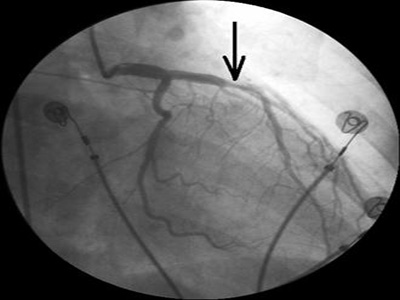

在保守組基礎上進行顱內血腫微創清除術,在CT下標志定點定出最大血腫層面的中心作起靶點,確定頭皮穿刺點,術前根據患者意識狀態給予鎮靜及止痛,常規備皮、消毒、鋪巾、局麻後,縱向切開頭皮約1cm,顱骨鑽鑽通顱骨及硬腦膜(鑽頭直徑5mm),然後用腦穿針進入血腫部位,從淺到深,用5ml注射器反復抽吸,抽吸血腫約占血腫總量的40%~60%。

用肝素100mg+生理鹽水250ml沖洗,每次≤5ml直至無陳舊性血腫抽出為止,如有新鮮血流出,可用冰生理鹽水加腎上腺素(生理鹽水100ml+腎上腺素1mg)進行沖洗,直至無新鮮血滲出。然後拔出腦穿針,置入腦室引流管(帶側孔)皮下固定接引流袋。

對於無新鮮出血者可注入尿激素酶2萬u,夾管2小時後開放引流每日1次,3~5天,經復查頭顱CT,血腫清除75%以上者拔除引流管。